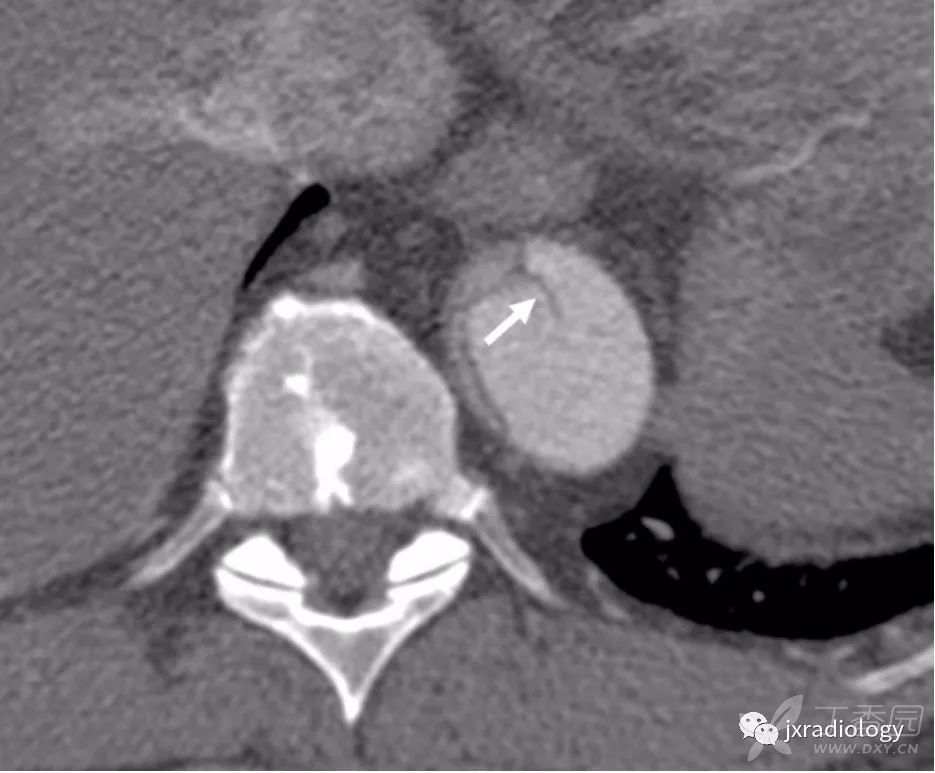

图6:升主动脉慢性夹层患者。

CT显示围绕假腔的壁钙化(箭头),提示慢性过程。